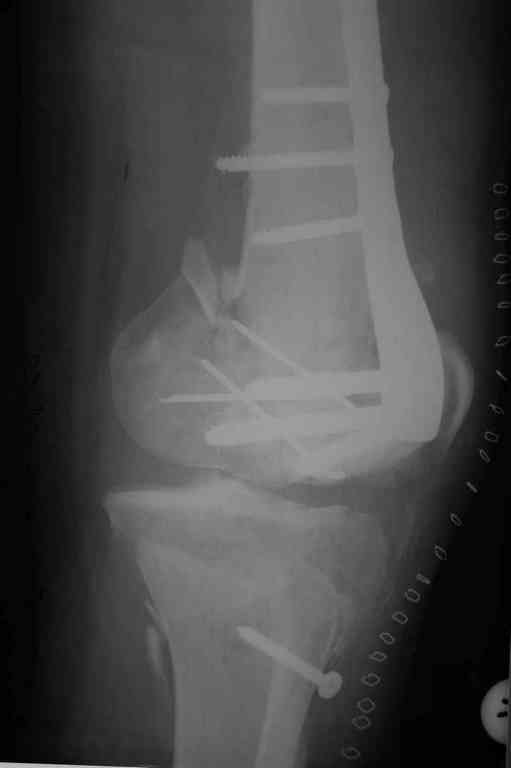

Здесь применение материала Plexur http://www.plexur.com для пластики при дефектах кости у больной с огнестрельной раной латерального тибиал плато с повреждением малоберцового нерва. Несмотря на интактный медиальный мышелок, для профилактики от вальгуса установлен АВФ и сделана ангиограмма.

После нескольких обработок и вакуумирования, поэтапно сделана фиксация тибиального бугра шурупами. И окончательную фиксацию закончили латеральной пластиной для тибиал плато и установкой пластического материала.

Для закрытия мягкотканых дефектов привлечена другая служба.

План с протезированием чересчур агрессивный, больная слишком молодая. В данный момент для удержания конструкции необходимо установить наружный фиксатор между бедром и голенью. Обработку продолжать с применением антибиотиков и вакуумирования.